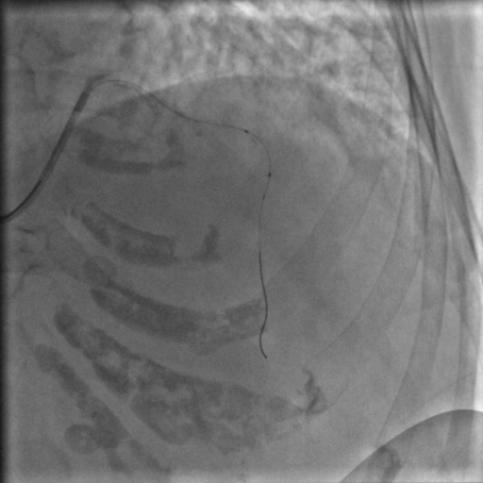

还是没通,这个也很正常。那就再拿球囊走一下,送入2.5*15mm的PTCA球囊,走得很顺,可以沿着导丝走到前降支远端,反复地走几次,看看能不能把血栓冲散,造影:

图8

还是没通,那就要来个血栓抽吸导管了,把球囊退出来,送入血栓抽吸导管到闭塞段,开始抽吸,一管、两管、三管,好了,看起来抽出来注射器里面都是血栓,抽吸的过程中似乎出现了一过性的心率变慢,应该是再灌注心律失常,应该通了吧,造影:

图9

好像前降支的显影是比刚才多出来一小节,然而依然还没通,那拿个球囊扩一下吧,把刚才的球囊送到闭塞段,2、4、6个大气压,轻轻扩一下,再轻轻扩一下,好松开,再打点硝酸甘油,造影: